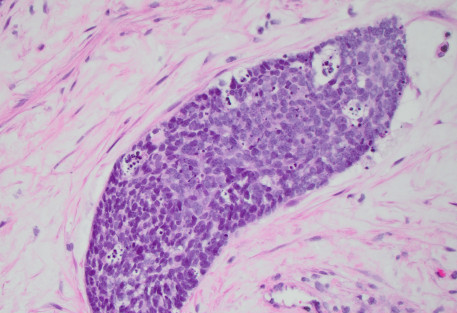

A liver biopsy was performed. H&E-stained sections of the liver biopsy demonstrated nests of malignant cells with scant cytoplasm and hyperchromatic, round nuclei. Numerous apoptotic bodies were seen (Figures 1, 2, and 3). Immunohistochemical stains were performed and the neoplastic cells were positive for cytokeratin AE1/AE3 (Figure 4), CD99, p16 (Figure 5), and INSM1 (focally positive). The neoplastic cells were negative for synaptophysin, chromogranin, and p40. High-risk human papillomavirus (HPV) in situ hybridization stain was positive. The Ki-67 labeling index was over 90% of the neoplastic cells. A concurrent biopsy of the uterine cervix was performed and had similar morphology to the liver lesion.